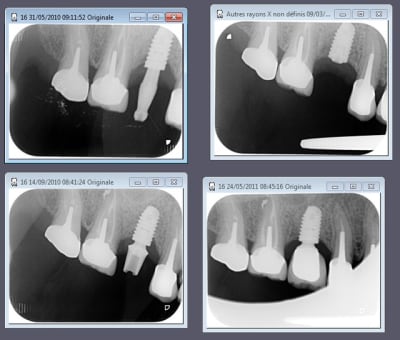

nouvelle radio cette semaine

c'est des krestals? Ça n'a pas l'air dramatique sur la radio. Une petite caractérisation qui me parait logique vu la connexion.

On n'a pas les mêmes critères d'exigences. Perdre 4 mm d'os sur 12 soit 1/3.

Attends, sur ces radios t'as 4 mm de perte osseuse? Les vis de cicatrisation sont en place non? Je devine la jonction implant/vis et y a quasiment pas de perte sur tes dernières radio. Enfin je connais pas bien le krestal et la forme de la vis.

Je veux dire, elle est où la perte osseuse sur cette radio? Mais tu as raison, on ne doit pas avoir les même exigences.

La cratérisation est visible beaucoup plus haute: surtout au sondage. L'os que tu vois est en palatin, en vestibulaire, il n'y a plus rien sur cette même longueur.

Sur la molaire, tu ne vois rien aussi.

EII et Mise en vitrine immédiate, ici implant très enfoui, premier cliché à 3 mois post-op puis à un an (il faut préciser que le contrôle de plaque est plus que parfaitement réalisé par le patient).

(implant Dentium superline avec état de surface SLA)

cas d'un axiom avec perte crestale et mise en charge en septembre voila l'évolution dans le temps la suite dans six mois